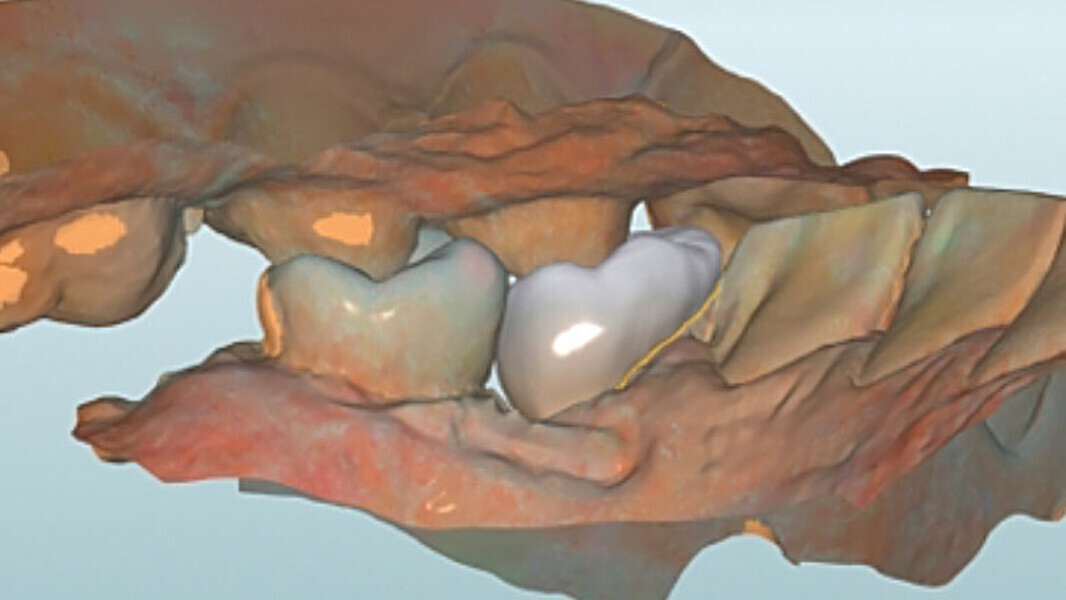

Fig. 8. Vista oclusal de la endocorona virtual en el software CAD.

Fig. 9. Vista lingual del diseño.